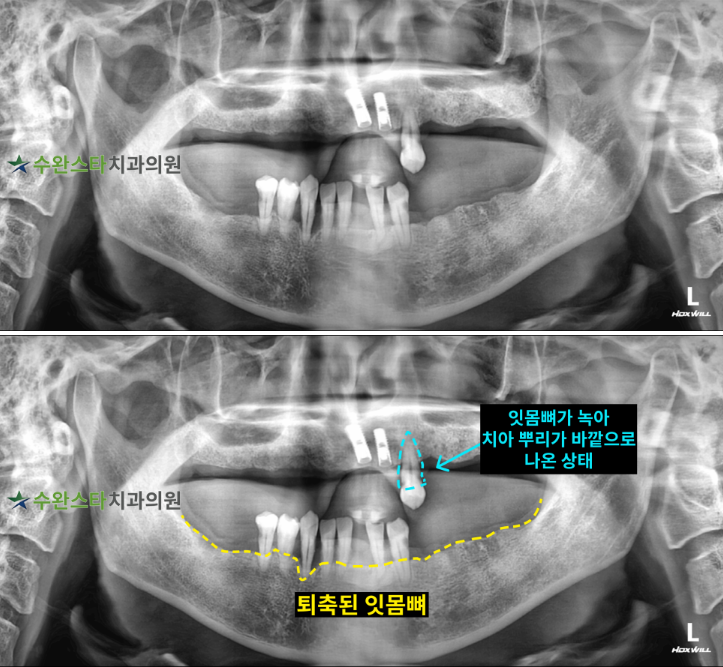

내원 시 파노라마

처음 내원 시 파노라마, 40대 남성 (2025.10 촬영)

내원 시 파노라마 사진입니다.

내원하셨을 때의 상태는

수직적인 치조골 흡수로 인해

많은 치아가 소실된 상태였습니다.

구강 내부 사진과 마찬가지로

하악에서 잇몸뼈가

녹아있는 게  관찰되었습니다.